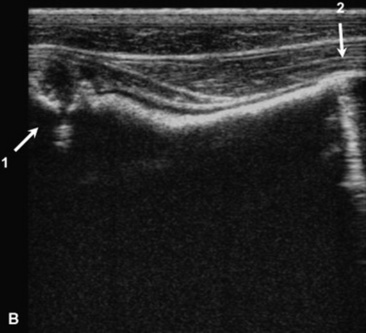

C. immitis is a soil saprophyte that grows in semiarid areas with sandy, alkaline soils.375 Inhaled arthroconidia enlarge to form nonbudding spherules, which incite an inflammatory reaction in the lungs and lymph nodes.375 Horses have weight loss, fever, abdominal pain, and signs of respiratory disease (Fig. 31-26). Localized, recurring nasal granulomas also have been reported.376 Diffuse infections with granulomas in the lungs, liver, kidney, or spleen carry a grave prognosis.375 Przewalskii horses may be more susceptible.377

image image image

Fig. 31-26 A, Coccidiomycosis in a quarter horse mare with severe weight loss after a 3-month period in Arizona and Colorado. Ultrasound image of free (B) pleural fluid and (C) abdominal fluid.

C. immitis is difficult to culture, and spherules may not be observed histologically from antemortem lung biopsies. However, serology is very useful to diagnose infection, and decreasing titers are associated with clinical improvement.332,375 Serum antibodies are detected rarely in healthy horses.378 Antifungal agents successful in treatment of infected horses include itraconazole and fluconazole.332,379